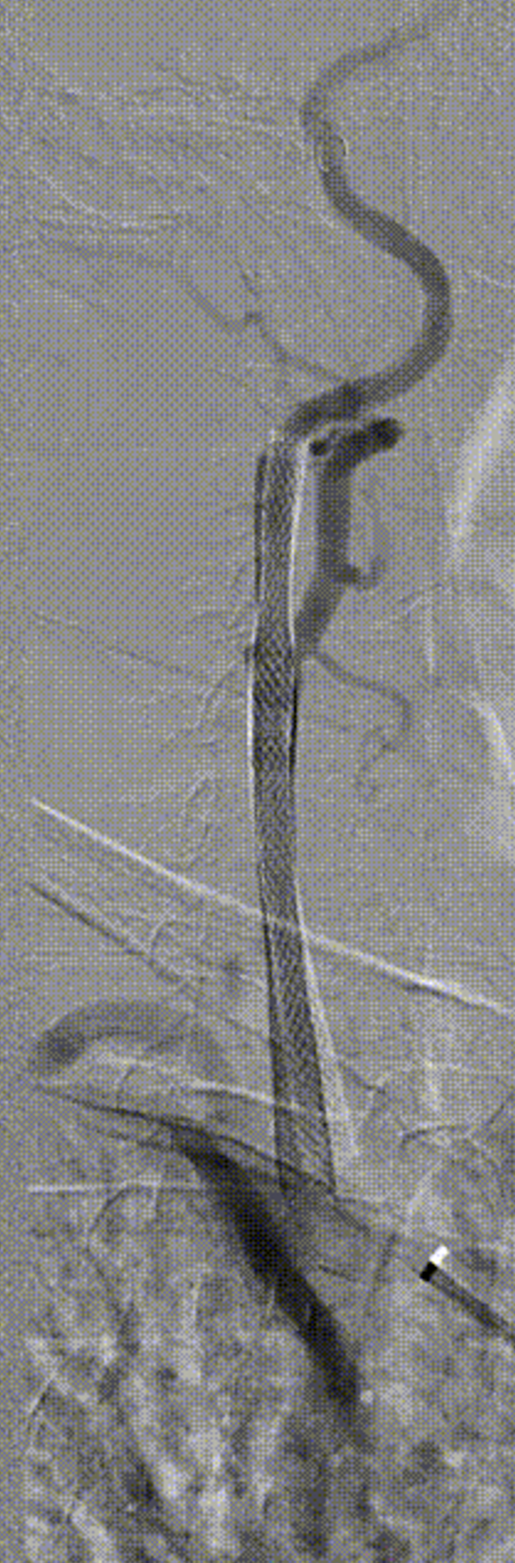

病例1:61岁男性,因双下肢间歇性跛行检查发现双侧颈动脉狭窄,冠脉情况严重,先行两次PCI,后行双侧CAS,先左后右,术后恢复良好。

左侧术前

左侧术后

右侧术前

右侧术后